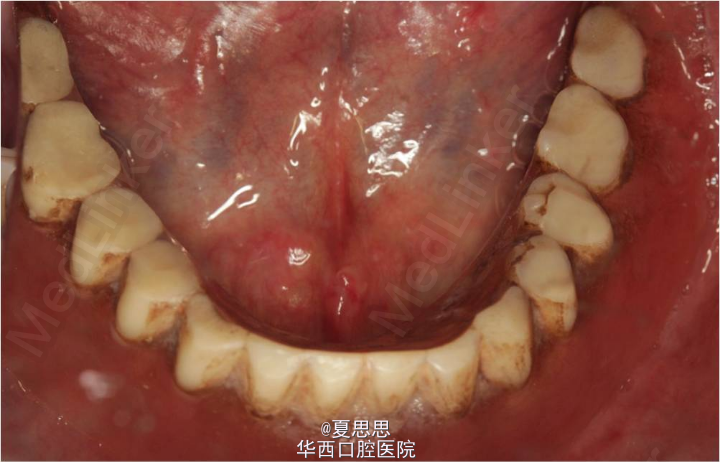

患者,男,40岁,上下颌牙列缺失10+年,现有义齿过度磨耗。患者10+年前因牙周炎致全口牙齿陆续脱落,后于我院行全口可摘义齿修复治疗,现有义齿过度磨耗,咀嚼功能下降,要求重新修复。

颌面部对称,面部比例协调,关节运动正常,侧面面型直面型。上下颌牙槽嵴丰满,颌弓卵圆形,上下颌弓关系正常,颌间距离中等,上下颌系带形状位置未见异常,腭穹窿形状高度适当,粘膜未见明显异常。